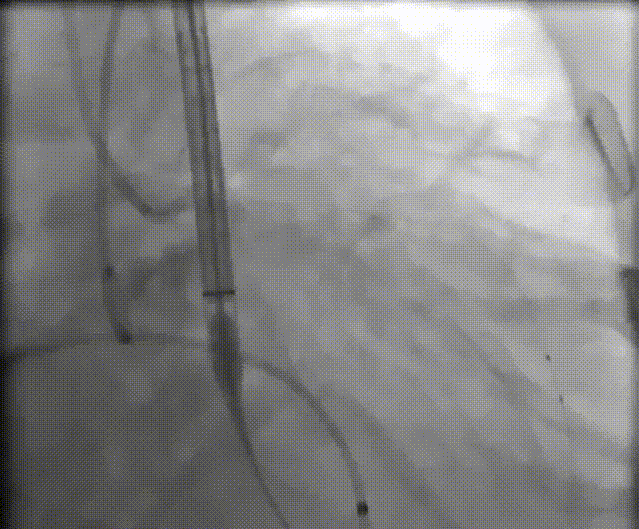

袁义强教授 河南省胸科医院(点击查看专家详细简历) 拥抱创新技术,推动心血管诊疗革新:作为医院管理者,我们团队始终把患者需求放在首位。干瓣作为TAVR的全新一代产品,其抗钙化性能预期为临床带来更卓越的耐久性,进一步延缓及降低二次手术的发生,每一个殷切期待眼神的患者身上,我们始终警醒,尽全力减少患者反复就医的痛苦,更从长远大幅节约医疗开支,让普通家庭看得起病、看好病。这不仅提升了诊疗效果,更践行了医疗惠民的初心,也多层面地减少医疗资源重复投入,为构建更经济高效的医疗体系注入动力,切实守护群众健康福祉。 孙玉梅教授 河南省胸科医院(点击查看专家详细简历) 念兹在兹,护佑患者每一刻:从医多年,我始终记得患者躺在病床上眼里饱含对健康渴求的殷切眼神,这是对医者的全心信赖——是把生命全然托付的信任,这份沉甸甸的情意,怎能辜负?选择什么手术策略,选择什么产品,医者需要给到专业意见的同时也需要听取患者的内心需求,既要保证当下手术的顺利成功,术后的快速恢复,更要为患者的长远生活兜底。Prostyle A 在这例重度钙化患者身上,既实现了术中安全植入、术后即刻改善,长久的抗钙化性能预期可以护航患者长期的生活。这份 “即刻与长久” 的平衡,正是我们一切从患者出发的初心写照,唯愿每一个细节里,都藏着让患者踏实的温度。 患者病史 主诉:间断胸闷、气促3年,加重两天。 既往史:平素健康状况良好。16 年前出现言语不清,就诊于当地医院,诊断为“脑梗死”给予药物治疗后症状好转。 术前 CT:Type1型(R-N)二叶瓣,右无交界存在钙化脊、粘连融合,极重度钙化,钙化集中在右无交界及三窦瓣叶边缘。 瓣环径27.1mm,LVOT28.9mm,瓣上3mm、6mm、9mm、12mm限制逐渐加重,从27mm逐渐缩窄至21mm。VTC空间较小,有一定冠脉风险。外周入路散在钙化、集中在双侧髂动脉与右股穿刺点后壁、双侧入路无明显迂曲,右股动脉内径可、低分叉。 手术策略 推荐右侧股动脉为主入路,瓣环27.1mm,Type1型(R-N)二叶瓣,右无交界存在钙化脊、粘连融合,极重度钙化,建议使用20mm球囊预扩,预装可回收AV23主动脉瓣膜,初始定位推荐真实瓣环上5mm超高位释放,释放时卸张力使瓣膜自然下滑至约瓣上1mm,利用瓣上限制固定瓣膜,提高封堵区封堵瓣上交界处,释放至工作位观察瓣膜情况决定是否回收。 手术过程 左右冠置入导丝进行冠脉保护 20号球囊预扩无明显腰征微量返流 初始定位 80%工作位观察 20号球囊后扩无明显腰征微量返流 术后造影:瓣膜形态好,有少量瓣周漏,冠脉造影无堵塞 术后超声:瓣膜形态好,有少量瓣周漏,平均跨瓣压差5mmHg Prostyle A®预装干瓣——“稳定支撑”助力临床最优化解决方案: 1. 平衡的径向支撑力:Prostyle A®综合设计带来平衡的径向支撑力,释放张力小,稳定贴靠,轻松应对高钙化病变; 2. Micro-EX™专利抗钙化技术:金仕生物专利抗钙化技术运用纳米技术去除组织内的细胞碎片和磷脂,封闭游离醛基,从根本上阻断了瓣膜钙化的多项因素,显著提升了瓣膜的耐久性;同时,相比较传统戊二醛保存方式,干式存储最大限度的保留心包的亲水亲油平衡,还原组织天然曲柔性,进一步保障了瓣叶开合,保证长期耐久性; 3. Prostyle A®平衡收腰设计:该例患者存在冠脉风险,Prostyle A®环上瓣及平衡的收腰设计,术后冠脉造影无堵塞,保证了有效瓣口面积的同时,带来更优异的血流动力学。